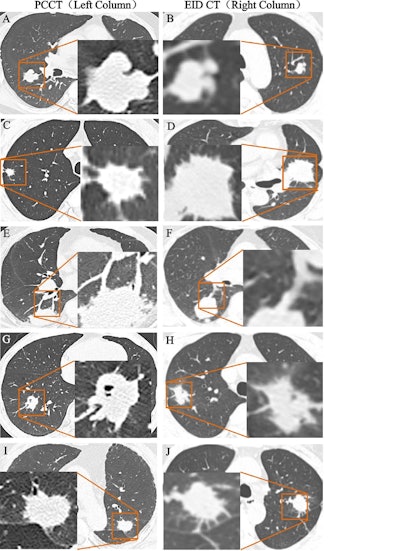

Representative imaging features of the lesion with energy-integrating detector (EID) CT and photon-counting CT (PCCT). (A) Unenhanced PCCT image (left column) in a 56-year-old man with lung cancer and (B) EID CT image (right column) in a 73-year-old man with lung cancer depict lobulation. (C) Unenhanced PCCT image (left column) in a 67-year-old man with lung cancer and (D) EID CT image (right column) in a 71-year-old woman with lung cancer depict spiculation. (E) Contrast-enhanced PCCT image (left column) in a 63-year-old man with lung cancer and (F) EID CT image (right column) in a 69-year-old woman with lung cancer depict vessel convergence. (G) Unenhanced PCCT image (left column) in a 64-year-old man and (H) EID CT image (right column) in a 49-year-old man with lung cancer depict vacuoles. (I) Unenhanced PCCT image (left column) in a 62-year-old man and (J) EID CT image (right column) in a 72-year-old man with lung cancer depict pleural retraction. The lung cancer lesions and their specific imaging features are shown in the orange boxes. In brief, compared with EID CT (B, D), PCCT provides superior visualization of contour bulge (A) and thick strands extending from the lesion edge (C), thereby enhancing the diagnostic confidence in identifying lobulation and spiculation. Vessel convergence and vacuoles are clearly depicted on PCCT images (E, G), but they appear blurred or indiscernible on EID CT images (F, H). Additionally, PCCT (I) shows clearer linear attenuation pulling of the fissure toward the lesion compared with EID CT (J), potentially improving the diagnostic confidence in pleural retraction.Representative imaging features of the lesion with energy-integrating detector (EID) CT and photon-counting CT (PCCT). (A) Unenhanced PCCT image (left column) in a 56-year-old man with lung cancer and (B) EID CT image (right column) in a 73-year-old man with lung cancer depict lobulation. (C) Unenhanced PCCT image (left column) in a 67-year-old man with lung cancer and (D) EID CT image (right column) in a 71-year-old woman with lung cancer depict spiculation. (E) Contrast-enhanced PCCT image (left column) in a 63-year-old man with lung cancer and (F) EID CT image (right column) in a 69-year-old woman with lung cancer depict vessel convergence. (G) Unenhanced PCCT image (left column) in a 64-year-old man and (H) EID CT image (right column) in a 49-year-old man with lung cancer depict vacuoles. (I) Unenhanced PCCT image (left column) in a 62-year-old man and (J) EID CT image (right column) in a 72-year-old man with lung cancer depict pleural retraction. The lung cancer lesions and their specific imaging features are shown in the orange boxes. In brief, compared with EID CT (B, D), PCCT provides superior visualization of contour bulge (A) and thick strands extending from the lesion edge (C), thereby enhancing the diagnostic confidence in identifying lobulation and spiculation. Vessel convergence and vacuoles are clearly depicted on PCCT images (E, G), but they appear blurred or indiscernible on EID CT images (F, H). Additionally, PCCT (I) shows clearer linear attenuation pulling of the fissure toward the lesion compared with EID CT (J), potentially improving the diagnostic confidence in pleural retraction.RSNA